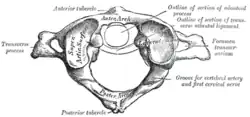

Wegen ihrer besonderen Lage und Beanspruchung besitzen der Atlas und auch der zweite Halswirbel, Axis (in der Klinik C2 abgekürzt), mit dem er eine funktionelle Einheit bildet, eine von den anderen Wirbeln verschiedene, spezialisierte Form.

Der Atlas hat entwicklungsgeschichtlich seinen Wirbelkörper verloren – dieser wird durch den Zahn des Axis repräsentiert – und ähnelt weitestgehend einem Ring. Innerhalb dieses Rings, und zwar auf der dorsalen Seite, verläuft vom Gehirn kommend das Rückenmark und setzt sich mitsamt seinen Hirnhäuten in dem mit dem Atlas beginnenden Wirbelkanal durch die Wirbelsäule fort.

Auf beiden Seiten leicht ventral ist der Ring wesentlich verdickt. Diese Verdickungen nennt man Massae laterales, auf deren Ober- und Unterseiten die Gelenkflächen zum Hinterhauptsbein (Facies articularis superior) und zum Axis (Facies articularis inferior) liegen.

Seitlich der Massae laterales liegen die kurzen seitlichen Fortsätze, Processus transversi. Sie gehen entwicklungsgeschichtlich aus den Processus costales hervor und besitzen – außer bei Wiederkäuern – die für alle Halswirbel typische, kleine Öffnung Foramen transversarium, durch die die Arteria vertebralis verläuft, die durch das Hinterhauptsloch (Foramen magnum) in den Kopf eintritt.

Im Gegensatz zu allen anderen Wirbeln besitzt der Atlas keinen Dornfortsatz (Processus spinosus), sondern anstelle dessen nur einen kleinen Höcker an der dorsalen Seite des Bogens (Tuberculum posterius) (bei Tieren Tuberculum dorsale). Auch an der gegenüberliegenden Vorderseite ist ein solcher kleiner Höcker vorhanden, das Tuberculum anterius.